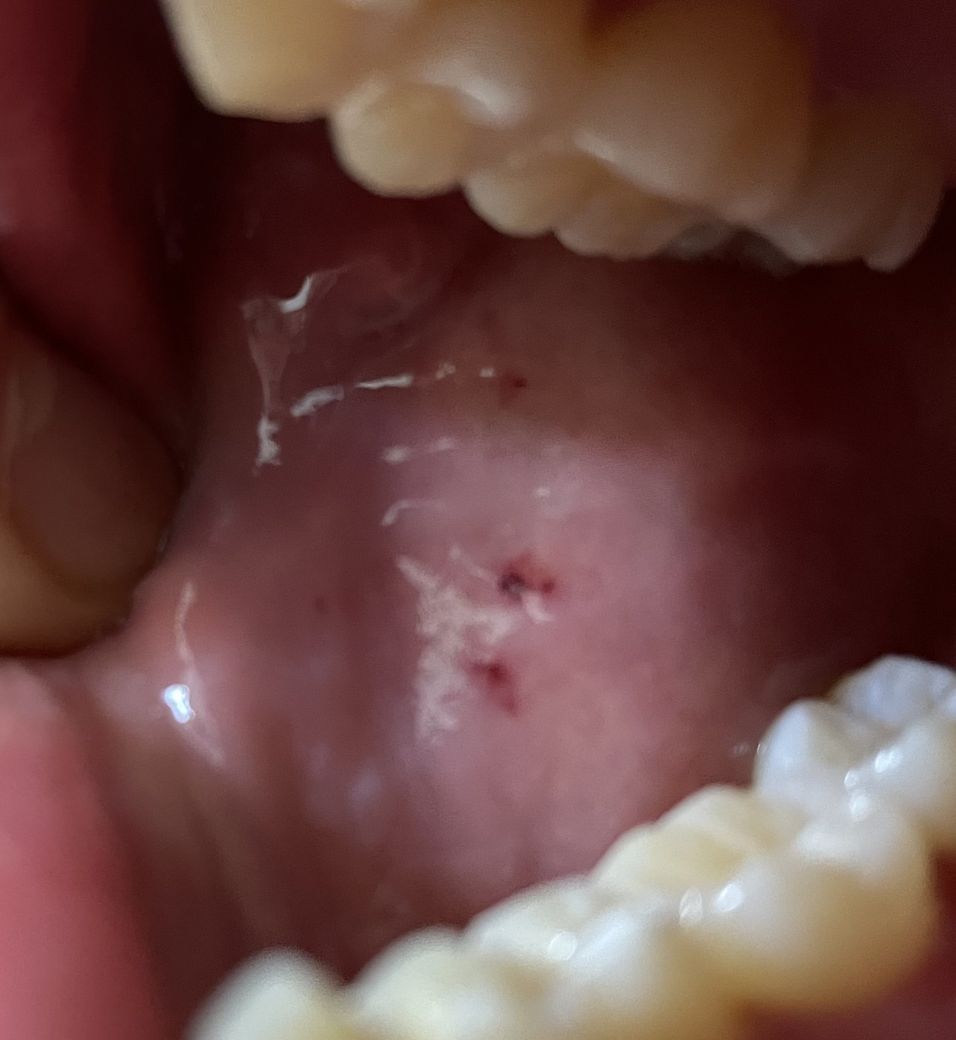

볼 안 쪽에 (입 안) 검은 점들이 생겼습니다 대체 이게 뭘까요?

구강암 증상을 찾아보니 그건 아닌 것 같고… 피 멍울이라는 글도 보았지만 제 증상과는 사뭇 다르게 생겼습니다. 내부 출혈이 있는 것처럼 검은 반점처럼 생겼는데 이게 대체 뭘까요? 피 멍울이 이미 터진 걸까요? ㅜㅜ 확실히 살짝 검붉은 게 피 느낌이 나는 것도 같습니다

첨부한 사진은 양쪽의 볼(안쪽)입니다 흔히 실수로 볼 씹었다 할 때의 그 부위 맞습니다

• 1번 째 사진

사진상으로는 상처처럼 보입니다. 보다 정확한 진단과 치료를 위해서 가까운 의원 혹은 병원 내원하셔서 전문의의 문진, 신체진찰 및 추가 영상학적 정밀검사를 해보시길 권유드립니다.

상기 증상은 암으로 보이지는 않고 깨물거나 손상에 의한 단순한 혈종으로 보입니다.

• 사진 소견만으로 구강암을 의심하기에는 무리가 있습니다. 악성 종양같아 보이는 종물도 관찰되지 않기 때문입니다. 단순히 피 멍울의 흔적일 수도 있으며 모르는 사이에 점막이 일시적인 손상을 받은 것일 수도 있습니다. 이비인후과에서 검진을 받아보시길 권고드립니다.